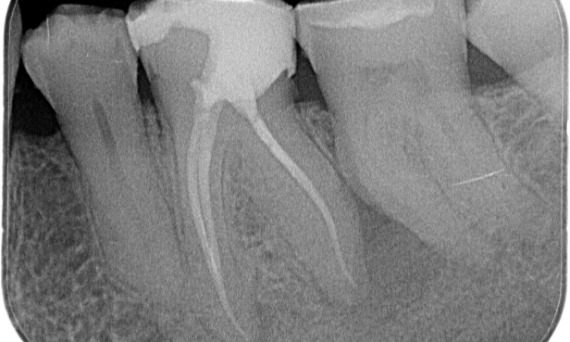

Antes: Radiolucencia periapical asociada principalmente con la raíz distal y pérdida de la lámina dura en la raíz mesial.

Después: En este caso, se eligió TruNatomy para permitir un enfoque apalancado en las caries y un enfoque en la conservación de la dentina pericervical, especialmente en el aspecto mesial donde el diente tuvo una restauración más mínima.

Antes: Tras el examen, hubo una lesión de caries relacionada con el primer molar inferior derecho. El examen radiográfico reveló la proximidad de la lesión a la bocina pulpar y, al combinarla con la queja principal, se concluyó un diagnóstico final de pulpitis irreversible crónica.

Después: La cavidad de acceso se realizó de la manera más conservadora posible. TruNatomy fue el sistema de elección debido a la edad del paciente joven. Necesitábamos preservar la dentina tanto como fuera posible para aumentar la capacidad del diente y así superar la carga oclusal y aumentar la longevidad de la restauración final.